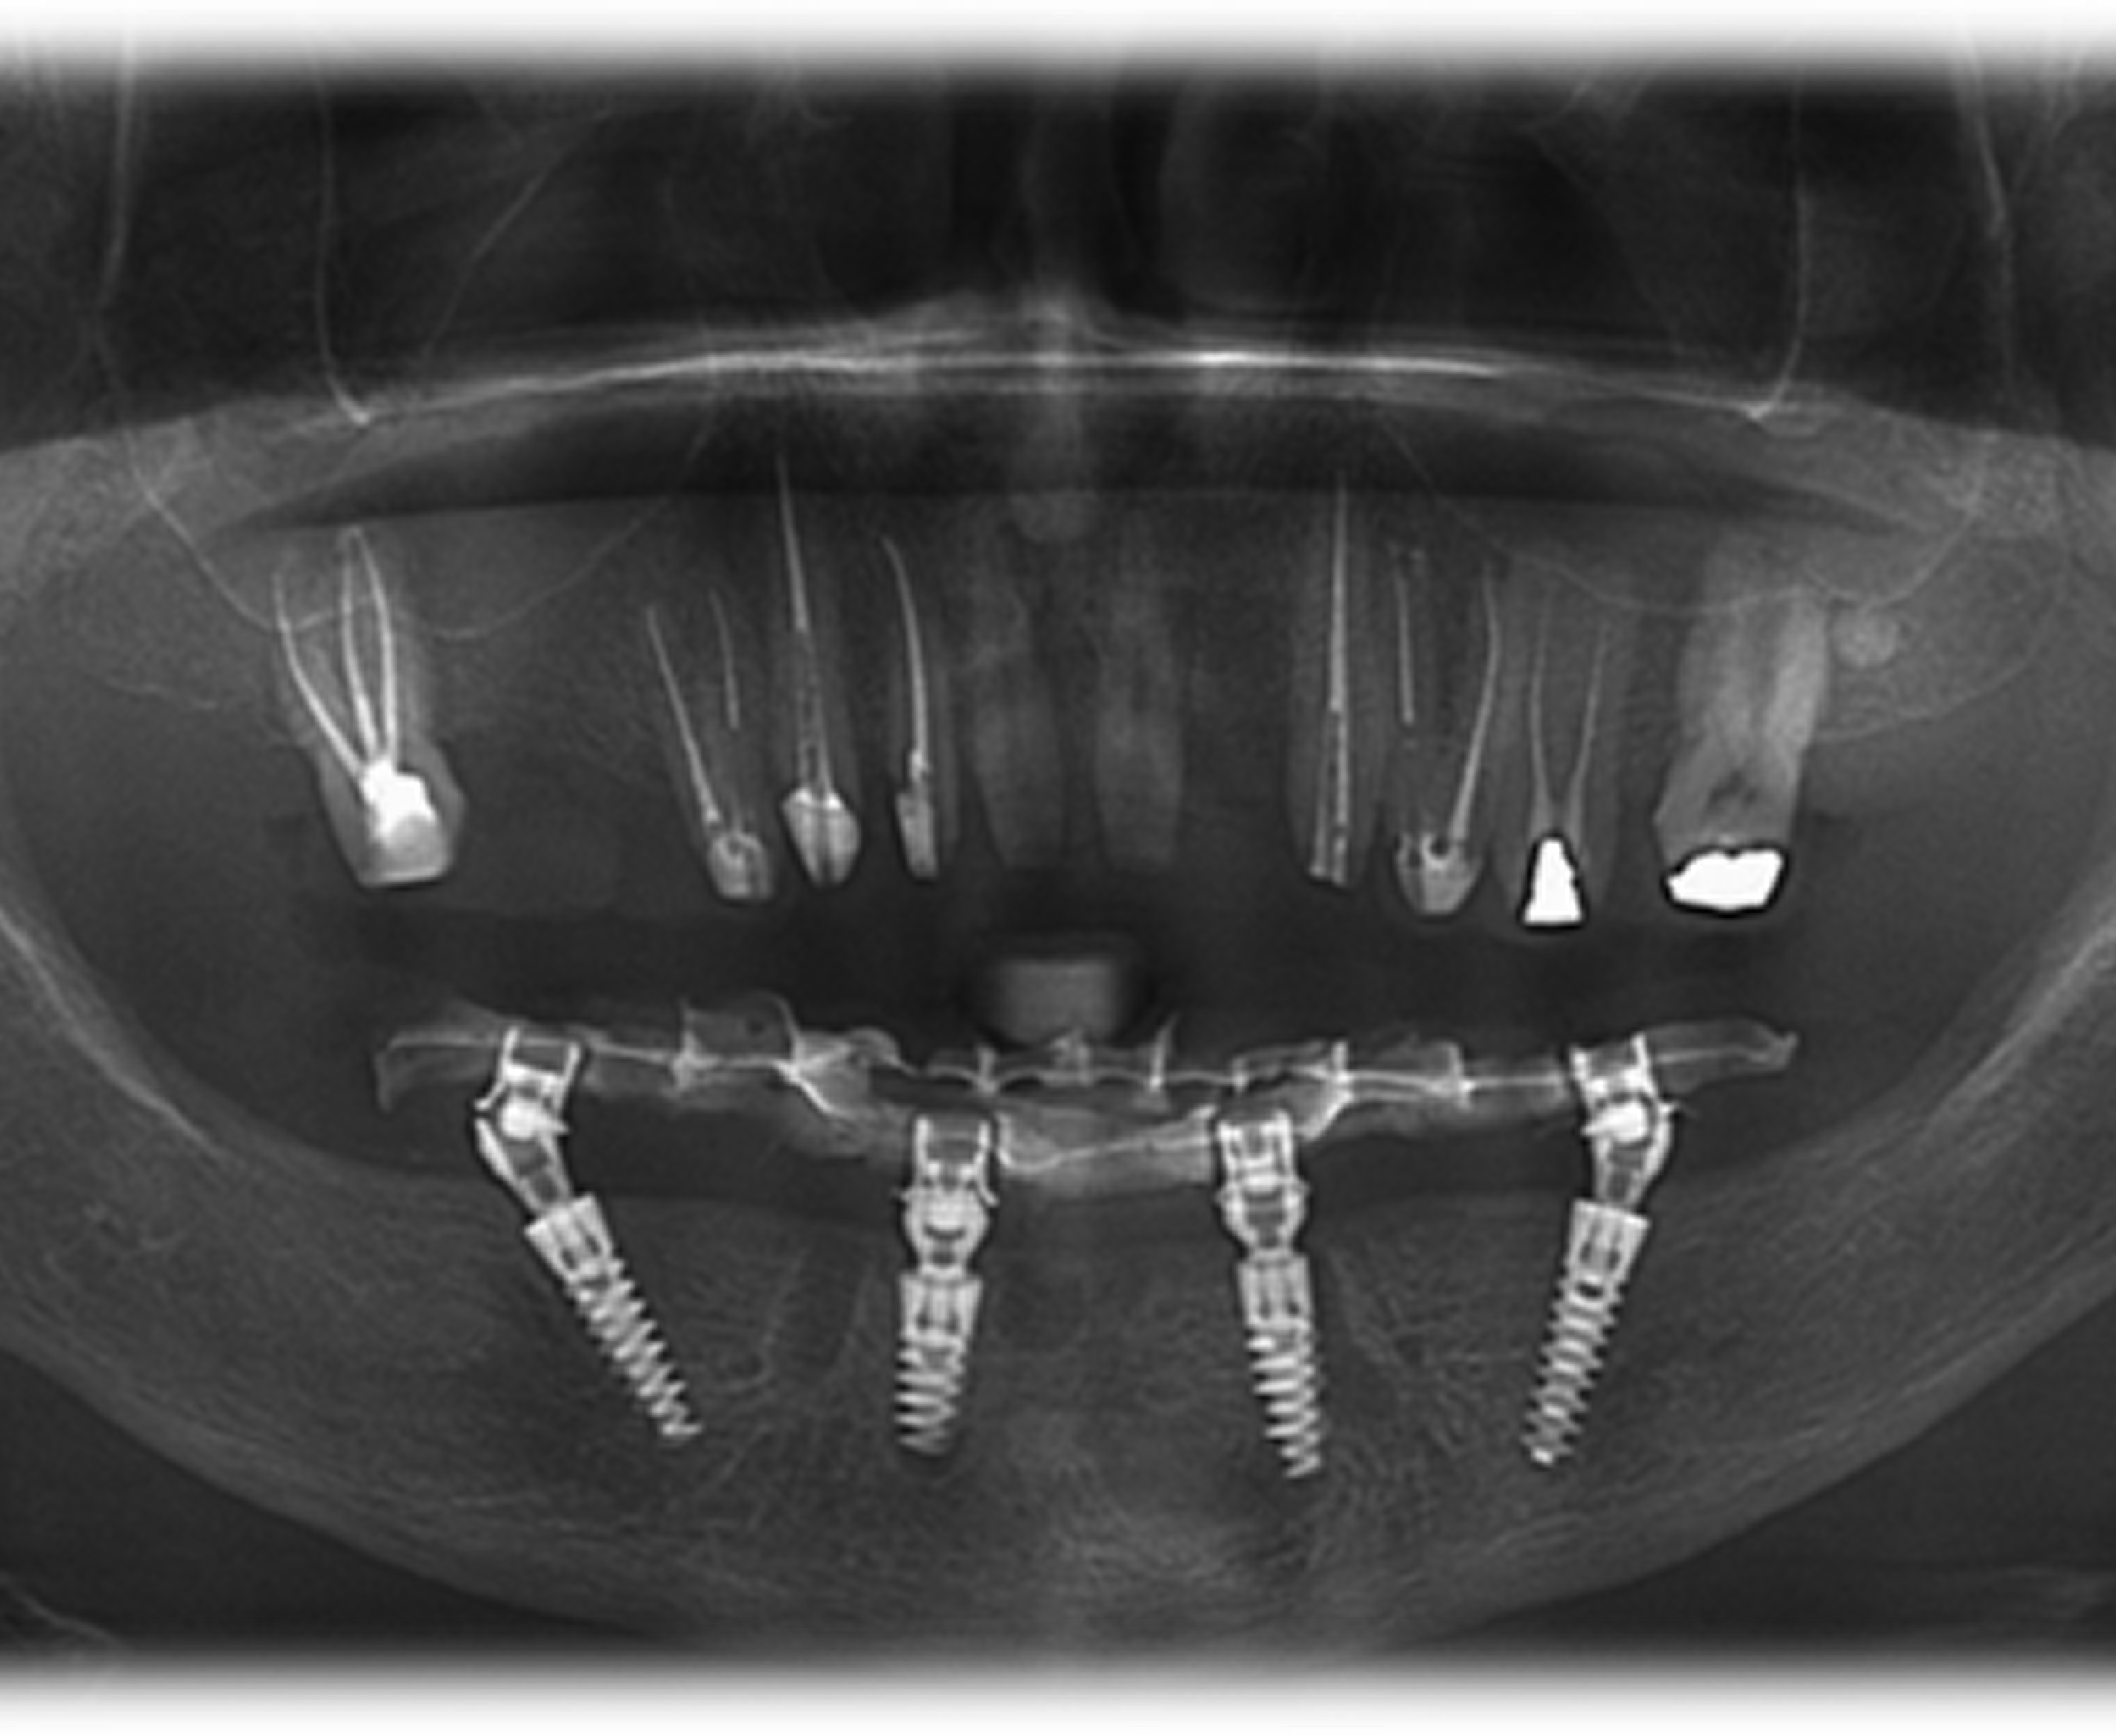

Day 1 — Digital Planning & CBCT Scan

- Full diagnostic imaging

- Precise digital planning for implant placement

- Design of guided surgical templates

- Placement of four strategically positioned implants

- Achieved strong primary stability, suitable for immediate loading